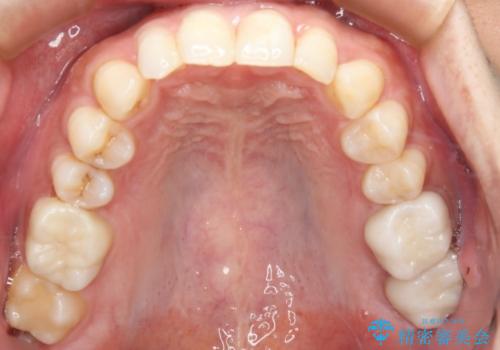

- 右上下6番の銀歯のやり変えを希望された患者様です。

切削量・形態を考慮し、上はセラミッククラウン、下はセラミックインレーでの治療を選択しました。

上はう蝕が歯頚部まで達していたのでクラウンでの治療を選択しました。

銀歯直下もう蝕が進行していたので全て除去した上でCRにて裏層しています。

下はクラウンほど切削量が多くないと判断し、インレーでの治療を選択しました。